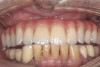

Fig 10. The full-arch zirconia framework with individual lithium-disilicate crowns, which were individually luted

in the laboratory.

Fig 11. Implant-supported full-arch zirconia bridge framework in situ.